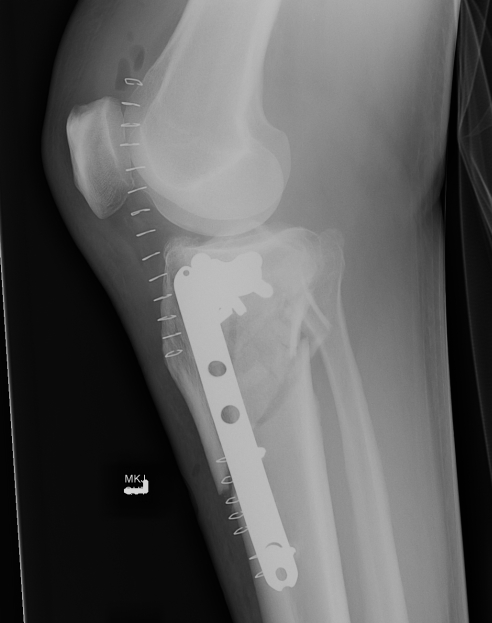

Type V Bicondylar

Options

1. Medial and Lateral plating

2. Circular Fixator

Technique

- depends on which of the three columns affected

- anterolateral approach for lateral column

- posteromedial appraoch for medial / posterior column